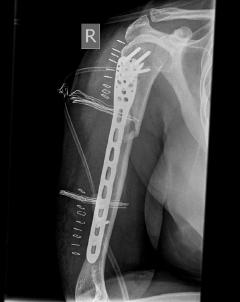

Κατάγματα μακρών οστών άνω και κάτω άκρου

Τα εν λόγω κατάγματα είναι αρκετά συνηθισμένα και συχνά συμβαίνουν μετά από τροχαία ατυχήματα ή πτώση από ύψος. Παρατηρείται εξαιρετικά μεγάλη ποικιλία στη μορφή τους, κατα κανόνα όμως είναι σοβαρά και πολλές φορές ανοικτά – δηλ με τραύμα στο σημείο του κατάγματος – κάτι που αυξάνει τον κίνδυνο λοίμωξης και επιβαρύνει την πορεία της θεραπείας. Στα κατάγματα των άνω άκρων ενδέχεται να υπάρξει και τραυματισμός νεύρων, που χρειάζεται επίσης αντιμετώπιση.

Με τα σύγχρονα μέσα που διαθέτουμε, όλα σχεδόν αυτά τα κατάγματα πρέπει να αντιμετωπίζονται χειρουργικώς. Υπάρχει πληθώρα υλικών οστεοσύνθεσης (πλάκες διαφόρων τύπων, ενδομυελικοί ήλοι, συστήματα εξωτερικής οστεοσύνθεσης) που είναι διαθέσιμα και επαφίεται στην εμπειρία του χειρουργού η επιλογή.

Οπως και άλλοι εξοικειωμένοι χειρουργοί διεθνώς, χρησιμοποιώ τεχνικές ελάχιστης παρέμβασης (Minimal Invasive Surgery), δηλαδή μικρές τομές, επειδή έτσι το χειρουργικό τραύμα είναι ελάχιστο, με αποτέλεσμα ταχύτερη επούλωση. Ταχύτερη πώρωση των καταγμάτων, ταχύτερη κινητοποίηση.

Περίπτωση 1ου ασθενούς